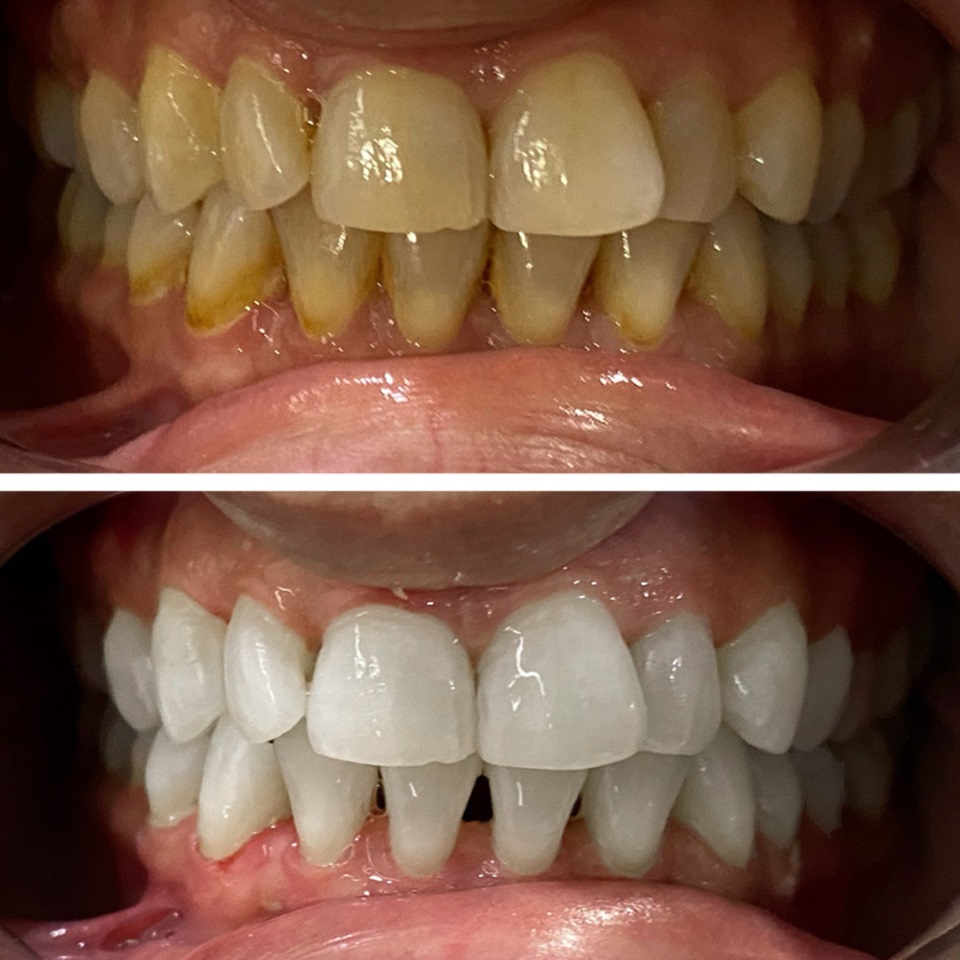

Smile Dental Clinic Turkey Gallery

Our Gallery and Happy Patients

Let’s make a change and put a perfect smile on your face with our dental clinic in Antalya/TURKEY.